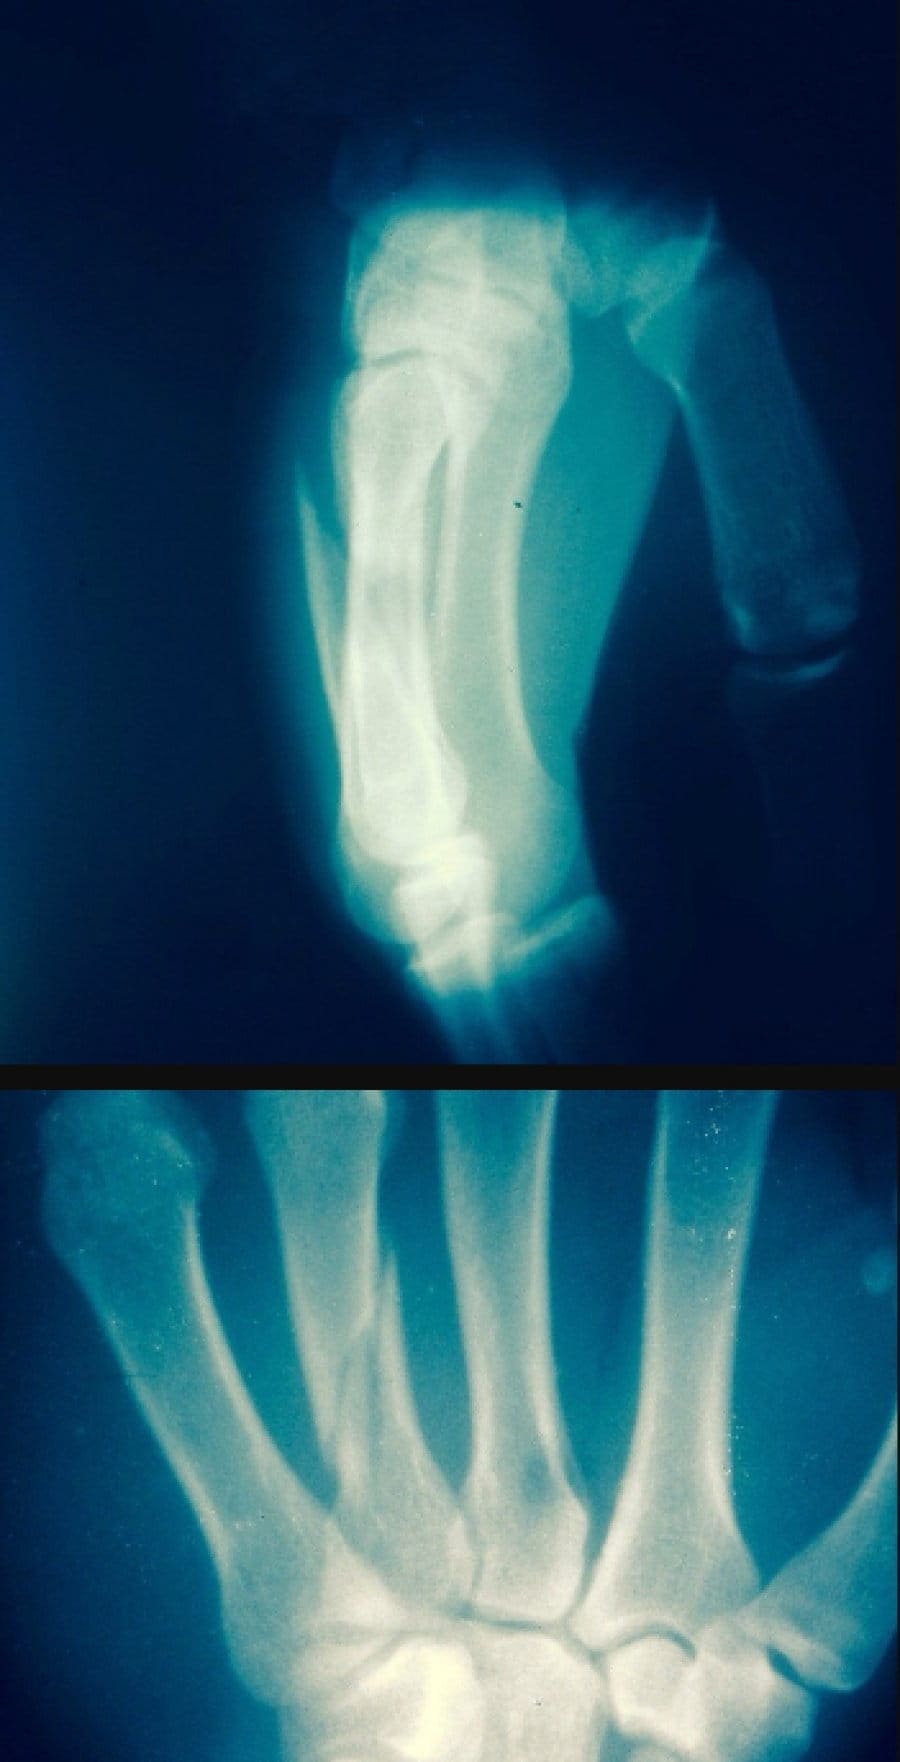

Перелом пальцев со смещением на левой руке и разрыв связок на правой помешали россиянину Туралу Рагимову продолжить бескомпромиссную битву за пояс чемпиона M-1 Challenge в полулегком весе со словаком Иваном Бучингером. Боец, его тренер и секунданты уже вернулись из больницы. На левую руку наложен гипс, правая - жестко зафиксирована, сообщает mixfight.ru.